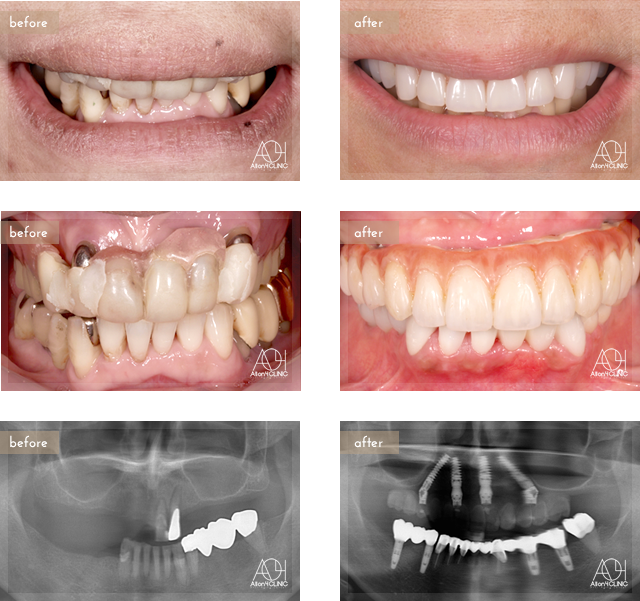

All-on-4

Age : 57

Sex : Female

Treatment : 2012

-Maxilla All-on-4

- Under -

上顎は5本のインプラントを埋入。上顎上部構造はチタンPIBフレーム人工歯タイプ(歯肉:アクリリックレジン 歯:人工歯)